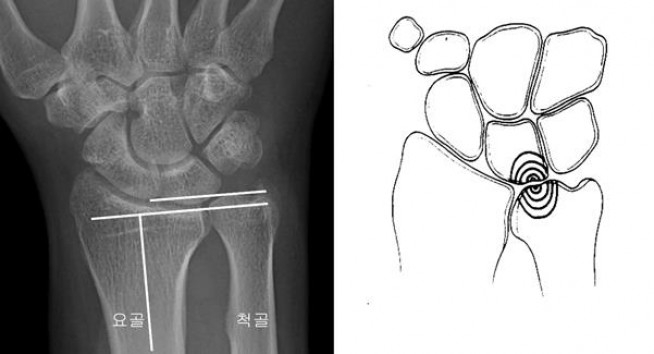

이재성 중앙대학교병원 정형외과 교수는 “척골충돌증후군은 퇴행성 관절질환으로 대개 팔뚝을 구성하는 두 뼈 중 하나인 척골이 요골에 비해 긴 경우 잘 발생한다. 손목을 쓰는 동적인 동작이 반복되면서 발생하는 경우가 많다”고 설명했다.

‘척골충돌증후군’은 손목관절의 지속적이고 반복적인 과부하로 팔뚝 안쪽 뼈인 척골두와 손바닥과 손목뼈로 구성된 수근골과 그 사이의 삼각섬유연골이 닳아서 손목 통증이 생기는 대표적인 퇴행성 질환이다. 문고리를 돌리거나 걸레를 짜거나 타자 등을 칠 때 손목 통증이 생긴다.

이재성 교수는 “새끼손가락 쪽의 손목에 튀어나온 뼈가 척골이다. 척골은 인대와 연골 조직의 복합체가 완충 작용을 하면서 손목뼈와 충돌하지 않는데, 손목을 비트는 동작이 빈번하면 척골두와 척측 수근골 사이에 삼각섬유연골 복합체 연골이 마모돼 통증이 발생하고, 이를 척골충돌증후군”이라고 말했다.

손목 척측은 많은 구조물이 세밀하게 기능을 하고 있어 ‘척골충돌증후군’은 반드시 다른 구조물 이상과 감별 진단을 해야 한다. 척골충돌증후군은 연골의 마모 또는 파열로 인해 통증이 있을 수 있는데 손목을 새끼손가락 방향 척골 쪽으로 꺾은 상태에서 통증이 생기거나 새끼손가락 쪽 손목뼈 사이 오목한 부위를 눌렀을 때 통증을 느낀다면 의심할 수 있으며, 병원에서는 촉진 등 이학적 검사 및 영상촬영 검사 등으로 진단할 수 있다.